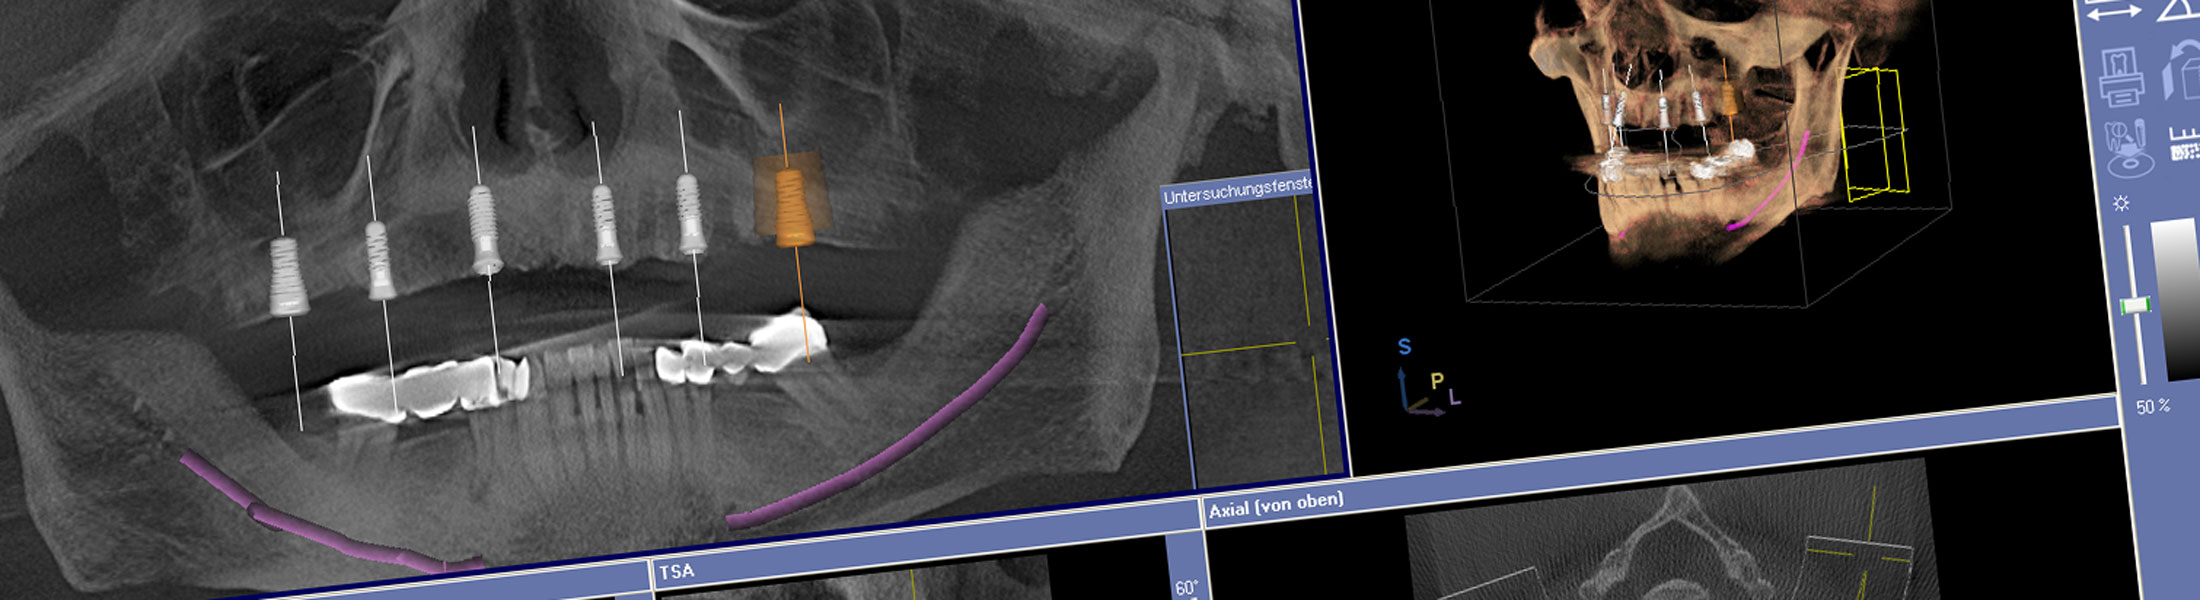

Ein Planungsprogramm liefert unseren Fachärzten detaillierte Informationen zur Knochendichte, Lage von Nervkanälen und zur genauen Position der Kieferhöhlen. Mit den Bildern der dreidimensionalen Diagnostik / DVT lassen sich der optimale Sitz des Implantats – die Position, der Winkel und die Tiefe – bestimmen Die Gefahr, dass Zahnwurzeln, Nachbarzähne, die Kieferhöhle oder Nerven bei der Implantation beschädigt werden, kann mit dieser Behandlungsmethode praktisch ausgeschlossen werden.